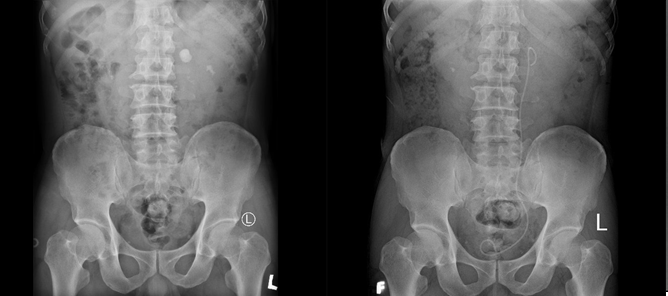

Sau mổ BN được rút dẫn lưu thận ở ngày thứ 3, rút sonde tiểu và chụp XQ kiểm tra lại ở ngày thứ 4, ra viện ở ngày thứ 5. Kết quả bệnh nhân sạch sỏi.

Hình 3 Hình ảnh sỏi thận T trước và sau phẫu thuật.

Tán sỏi thận qua da đã có ưu điểm vượt trội như đường tiếp cận vào nhỏ, mất máu ít mà hiệu quả thật sự tốt ( Hình 3 ) đặc biệt trong những ca bệnh có bất thường về giải phẫu như thận móng ngựa, với các bất thường về giải phẫu như tăng số lượng mạch máu thận, vị trí xoay trước của bể thận. So với phương pháp mổ mở truyền thống để tiếp cận bể thận T là rất khó khăn có thể gây mất máu nhiều mà không đạt được hiệu quả lấy sỏi thận, tán sỏi qua da có ưu điểm vượt trội.